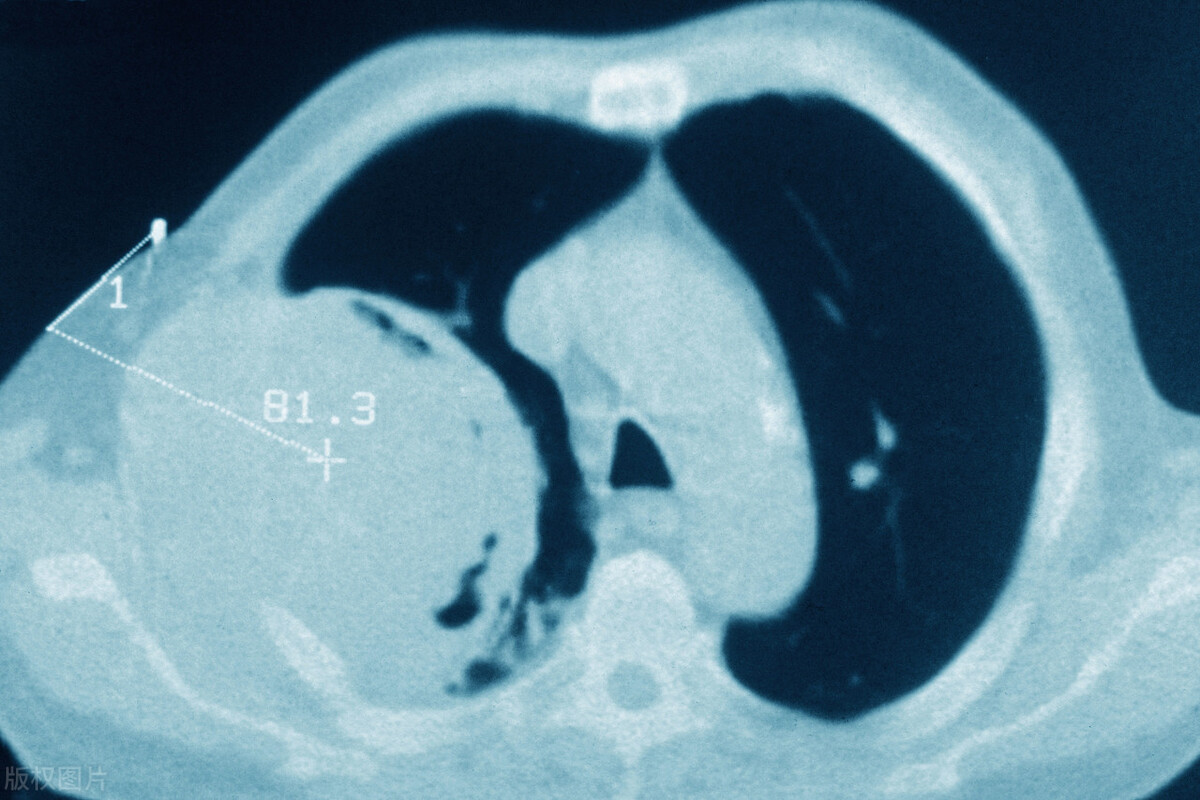

CT结果显示,李先生的肺部有一个肿瘤,大小约为4厘米。李先生对此非常惊讶,因为他并不是烟民,也没有咳嗽或胸闷等典型的肺癌症状。

影像学检查: 通过X线、CT、MRI等影像学技术,对肺部、心脏、肝脏等器官进行检查,以了解是否存在肿瘤、结构异常等情况。